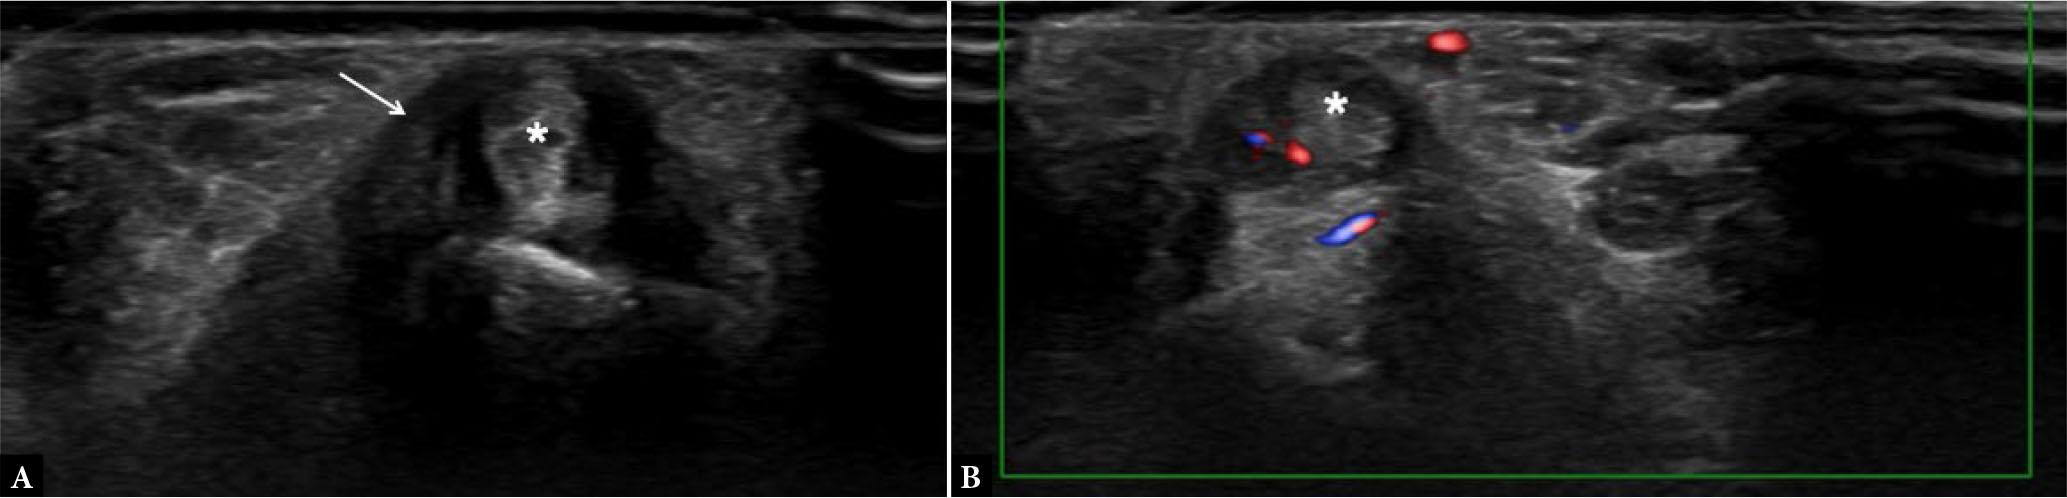

Fig. 12.

Extensor carpi ulnaris (ECU) tenosynovitis. Short-axis grayscale (A) and power Doppler (B) US of the ECU (asterisks) shows sheath thickening (arrow in A) with power Doppler signal keeping with tenosynovitis, in a patient with RA